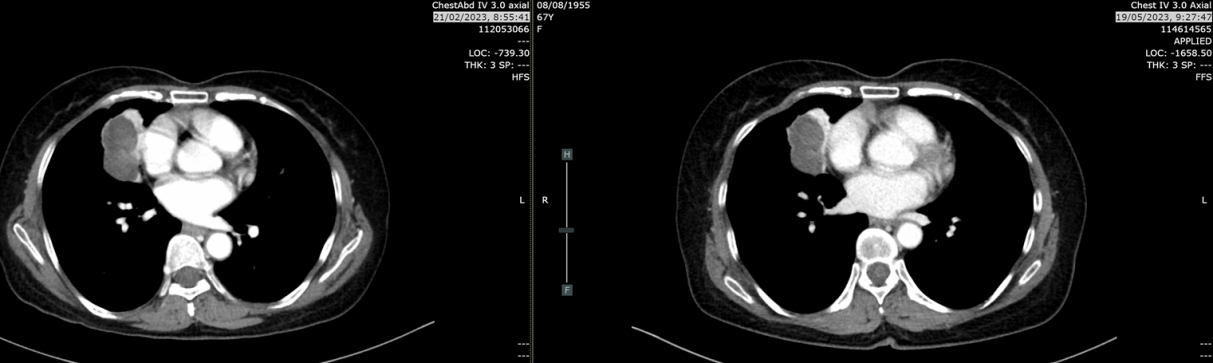

胸部增强CT(2021-12-21):右肺中叶及右肺下叶前基底段巨大软组织密度肿块,大小约6.8×6.3×8.5cm,边界不清;右肺上叶及下叶多发磨玻璃结节(最大1.0cm),考虑肺内转移;纵隔及双侧腋窝多发淋巴结融合肿大;左侧肾上腺见0.9×0.8cm低密度结节,可疑转移。气管及主支气管通畅,无胸腔积液,无骨破坏。

复查CT(2022-03-07):肿块增大至8.9cm,伴阻塞性肺炎,多发淋巴结最大达3.4cm。

复查CT(2022-04-05):肿块进展至9.4×7.7×7.1cm,侵犯右侧叶间裂、膈肌、胸壁及心包(脂肪间隙消失)。右肺多发纯磨玻璃结节0.4-1.0cm,考虑原位腺癌或非典型腺瘤样增生。纵隔淋巴结分布于右肺门、隆突下、右上及下气管旁区域,以及左上气管旁区域,最大3.3cm(隆突下)。

复查CT(2023-02-21):肿块5.3cm,仍维持PR状态。

复查CT(2023-05-19):肿块4.3cm,淋巴结缩小至0.8cm,无肝/肾上腺转移。